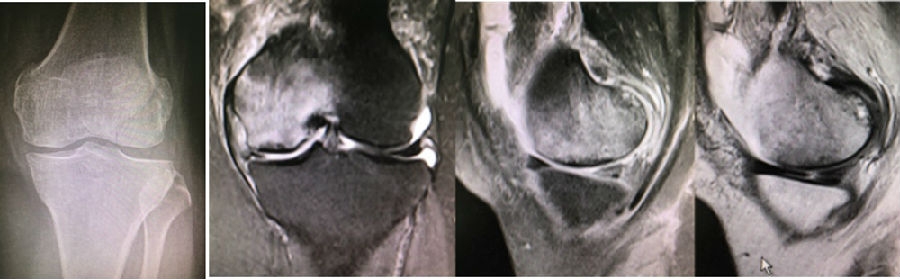

关于影像学评估与SONK的预后的关系,多项研究表明小于3.5cm2的小坏死病变可进行保守治疗,在冠状位X片上5cm2软骨下病变面积作为预测预后不良和高风险进展的临界值,前后位X片坏死区>50%髁,会迅速塌陷,病变范围很大(>40%髁/前后位X 片)或有早期骨关节炎的影像表现,保守欠佳。

早期(3月内)内侧半月板相对挤压百分比≥33%,是SONK发病1年后预后不良的预测指标,MRI检查没有局灶性轮廓塌陷和髁深处没有低信号线(隔离带),预后好,股胫角>180°(下肢力线内翻>6°)和MRI上深度>20mm 预示SONK患者症状发作后1年预后不良。

a.患者,59岁女性,AP侧位片显示SONKⅠ期,FTA<180°;b.MRI T2显示病变深度<20mm,患者出现症状1年后保守治疗;c.75岁女性,X线显示SONKⅠ期,FTA>180°;d. MRI T2显示病变深度>20mm,患者于症状出现后11周行手术治疗